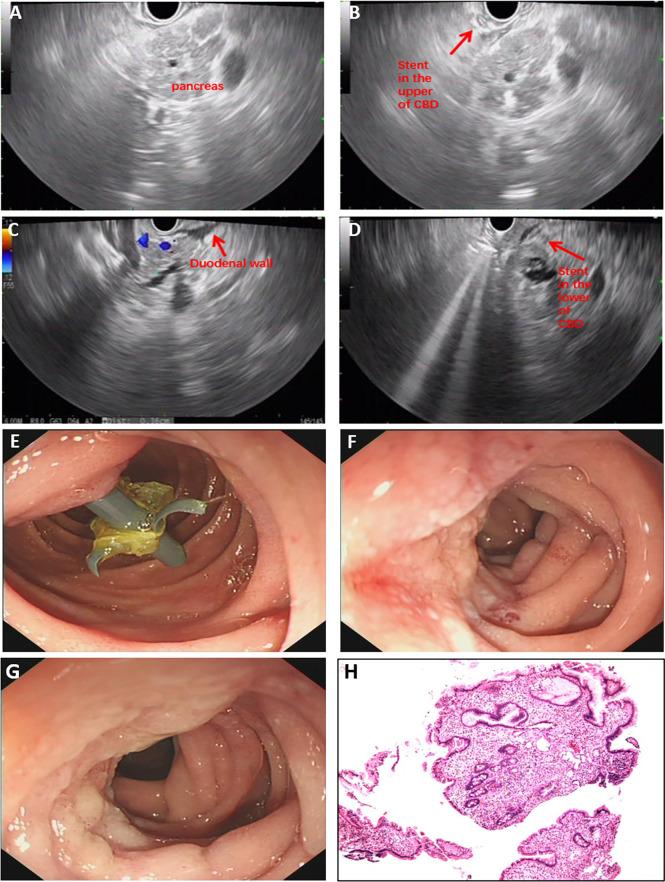

A 57-year-old male patient was transferred to our hospital after endoscopic retrograde cholangiopancreatography (ERCP) with stent placement in the common bile duct due to obstructive jaundice at a local hospital. Groove pancreatitis was considered based on the clinical manifestations and multiple examinations [including computed tomography (CT), magnetic resonance cholangiopancreatography (MRCP), and endoscopic ultrasonography (EUS)]. The patient's symptoms and laboratory results almost returned to normal after conservative treatments. Interestingly, his symptoms and laboratory results worsened after the stent was removed. We performed a second EUS process and found a lesion in the lower common bile duct. Finally, the patient underwent pancreatoduodenectomy, and the diagnosis was confirmed as moderately differentiated adenocarcinoma of the common bile duct.